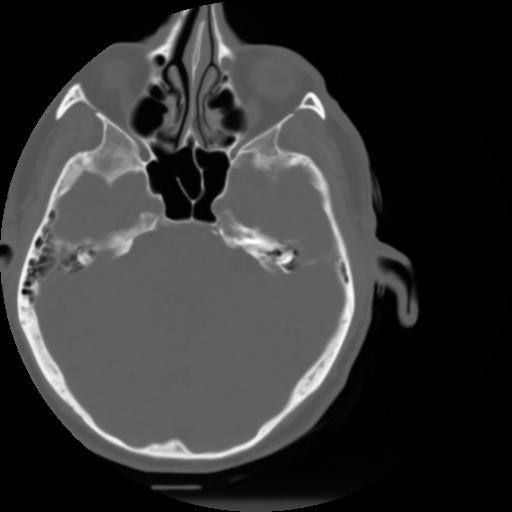

3 CEREBRO,,Axial,3.0,CEREBRO,,